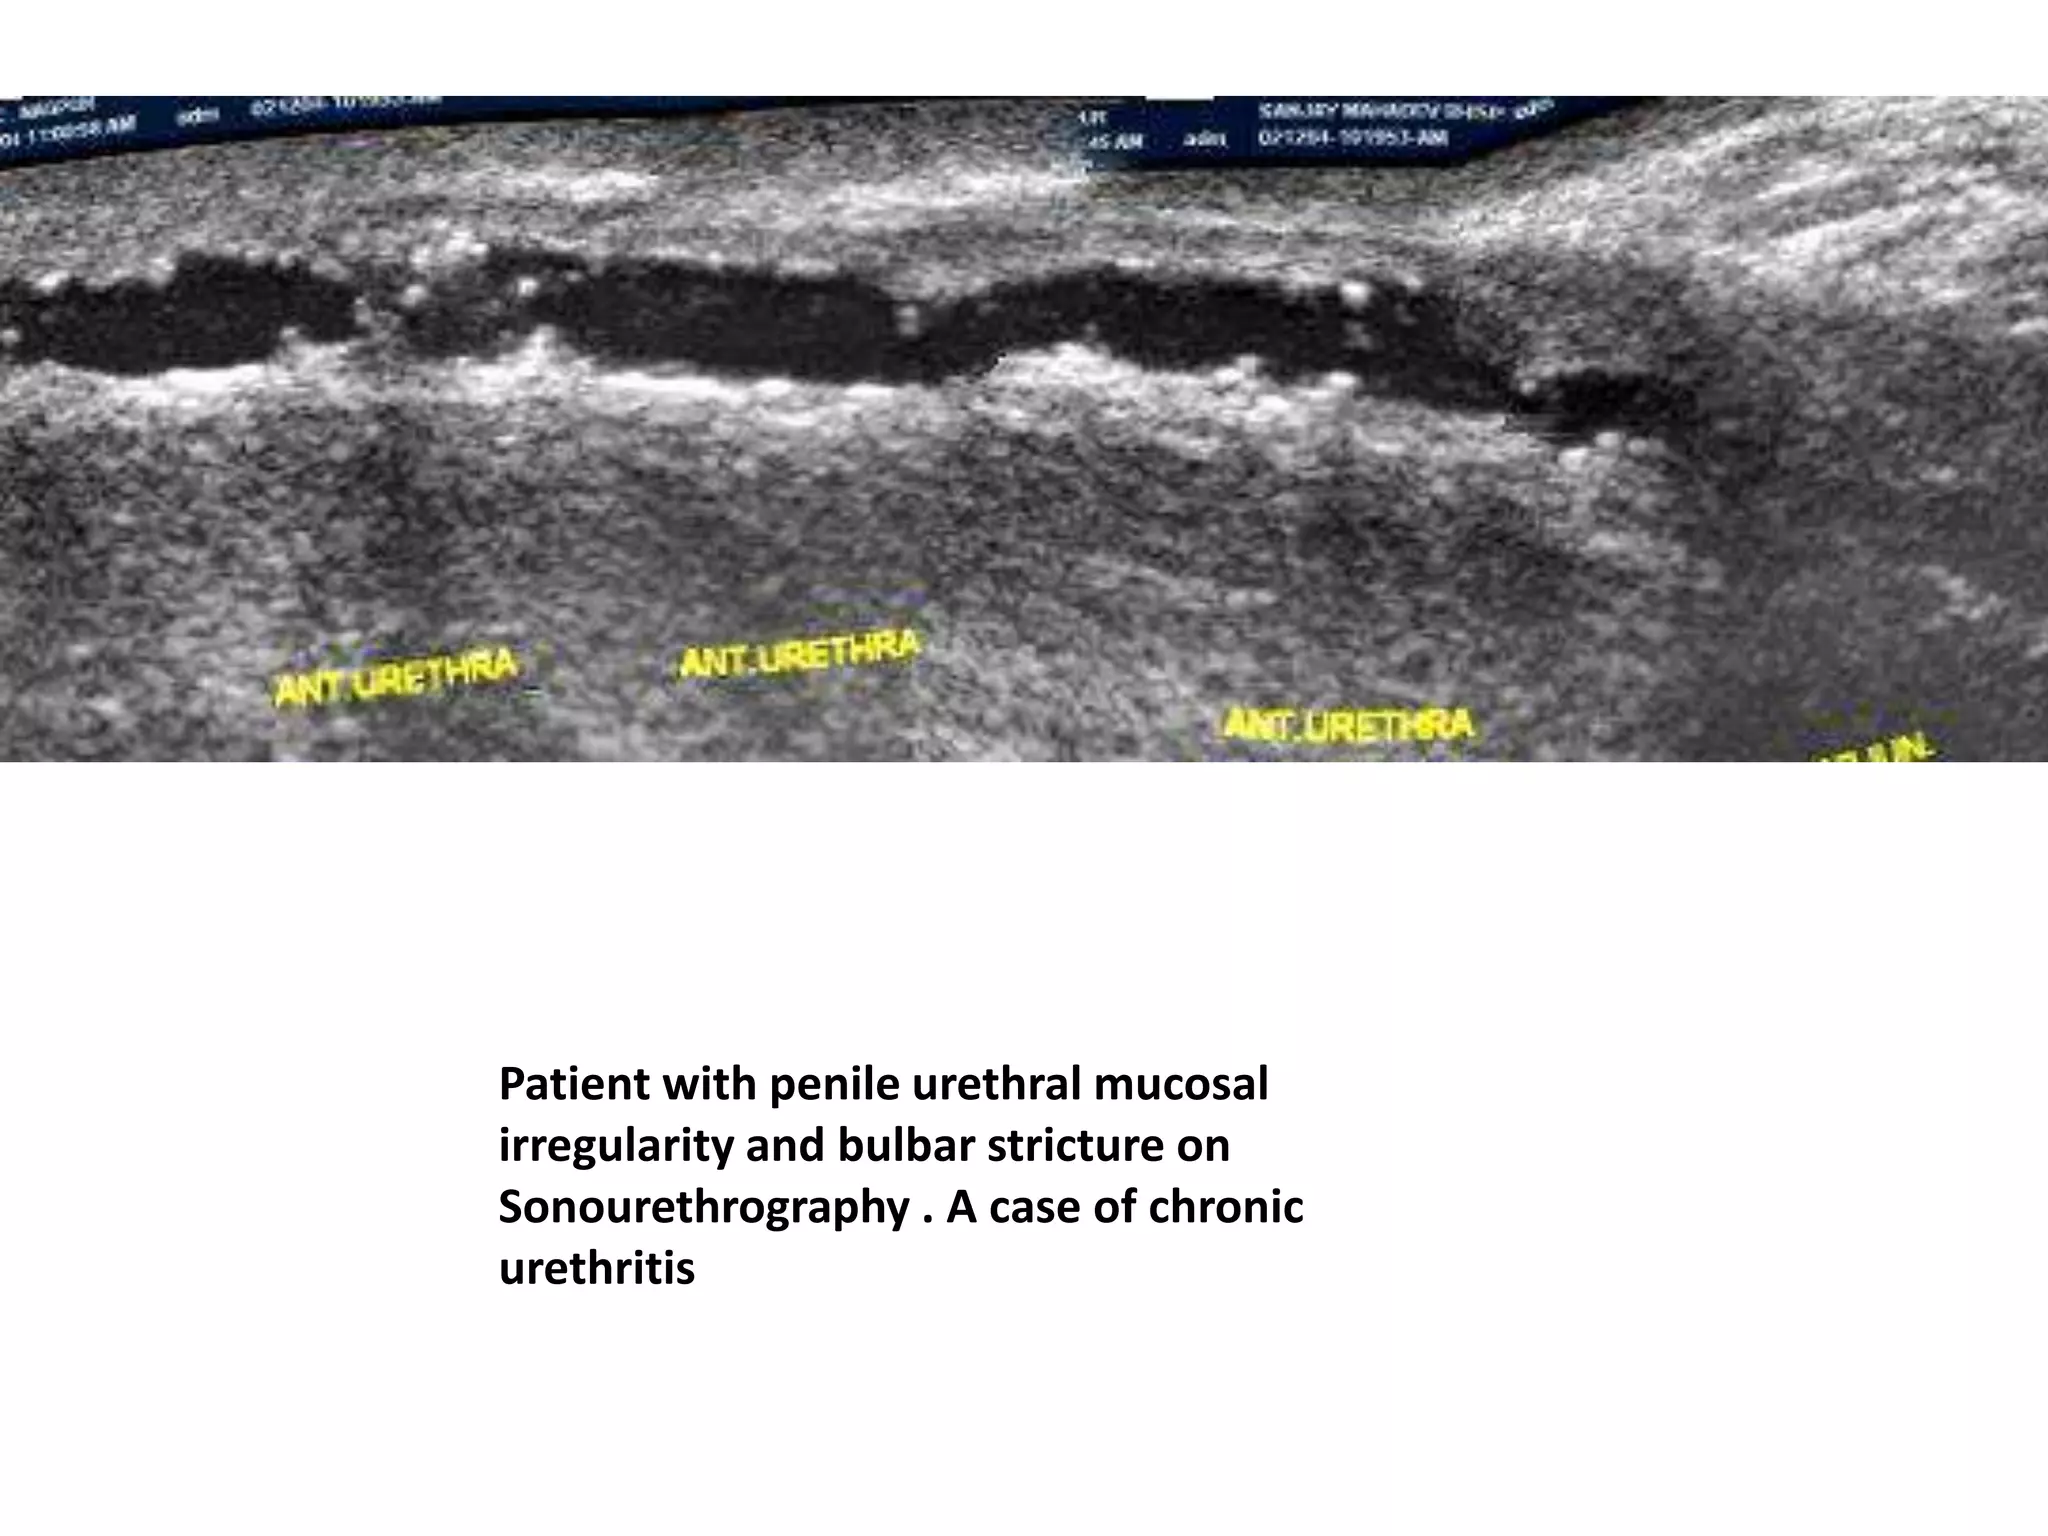

Patient with penile urethral mucosal

irregularity and bulbar stricture on

Sonourethrography . A case of chronic

urethritis

Patient with penileurethral mucosal irregularity and bulbar stricture on Sonourethrography . A case of chronic urethritis